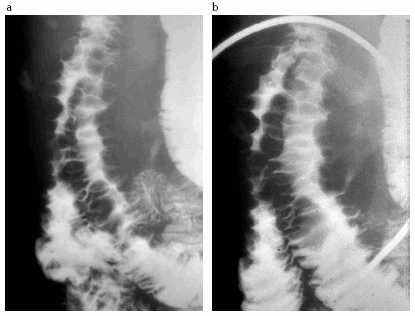

Sx Huella digital